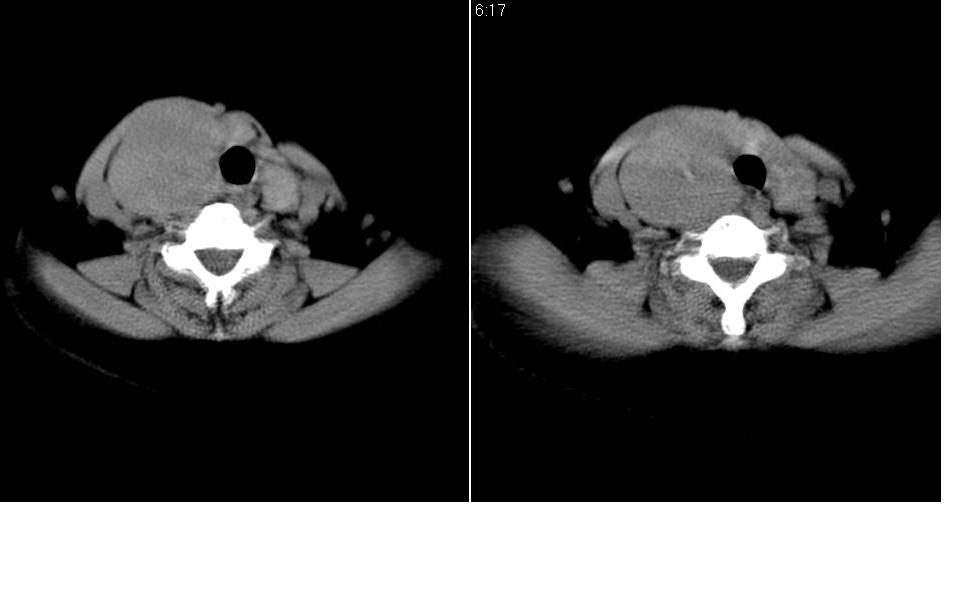

标题: CT27207:颈部CT平扫

女 55岁 右侧颈部包块十年余,自己感觉有增大。

来源于右侧甲状腺  边界清晰,内可见点状钙化,向下生长达前上纵隔血管间隙内  考虑甲状腺腺瘤并胸内甲状腺肿